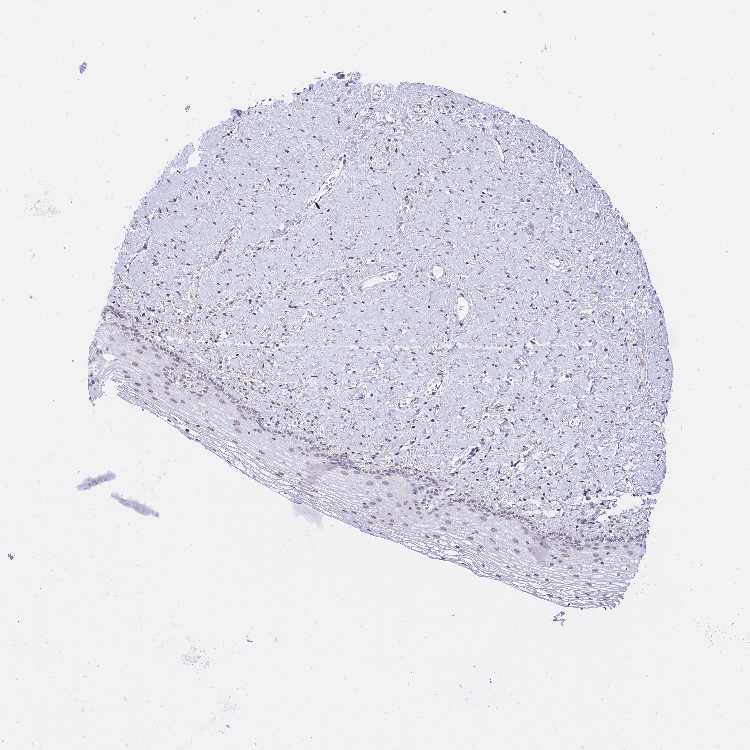

KCTD13